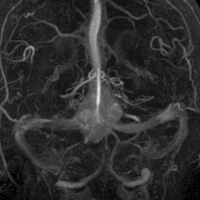

- 椎骨動脈撮影では,著明な腫瘍濃染像(血管がいっぱい)がみられて確定診断が可能です

左小脳にできた小さな のう胞性血管芽腫です。矢印の先にある小さな塊だけが腫瘍で周囲は腫瘍から染み出した液体が溜まっています(のう胞といいます)。右側は血管撮影とMRIを組み合わせた画像で,腫瘍に動脈が流入しているのが見えます。

真偽のほどは解りませんが頭の中で血液が流れる音がするというのが主訴です。その後に軽度の歩行失調と構語障害が出て発見されました。この程度のものでもAVMと同じように血管雑音を自覚することがあるのかもしれません。画像をよく見ると右の小脳扁桃のもので,延髄はただ圧迫されているだけです。血管芽腫はエリスロポエチンを産生して多血症になることがあるのですが,この患者さんは16.6 MIU/mlで正常値でした。

右のPICAが主たるfeeding arteryです。でもPICAのretromedullary segmentからshort feedersが流入していますから,油断をすると延髄背側障害という厳しい手術合併症を生じる可能性は十分あります。この腫瘍は正中後頭下開頭で全摘出できましたし,神経脱落症状を残していません。難易度は中等度のものです。